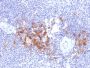

This MAb recognizes a protein of 52 kDa, which is identified as TNFR1 (TNFR-associated factor 1). CD30-positive lymphoproliferations of the skin comprise 30% of all primary cutaneous T-cell lymphomas (CTCLs). Besides borderline cases this group includes lymphomatoid papulosis (LyP) and primary cutaneous anaplastic large T-cell lymphoma (cALCL). Although the two entities overlap clinically, histopathologically, immunopathologically and genetically, they differ considerably in their prognosis. In particular, common feature of both cases is histologically the presence of atypical lymphoid CD30-positive T blasts and genetically a clonal T-cell-receptor rearrangement. However, both cases differ considerably in their clinical course: Lesions of LyP regress spontaneously, whereas those of cALCL persist and may progress and spread. Moreover, LyP patients do not benefit from an aggressive radio- and/or chemotherapeutic approach, in contrast to patients with cALCL. Besides, LyP and cALCL differ strongly in the expression of TRAF1 (tumor necrosis factor receptor (TNFR)-associated factor 1), a component of TNFR signaling: Whereas tumor cells of most LyP cases (ca. 84%) show a strong TRAF1 expression, tumor cells of cALCL reveal TRAF1 expression in only a few cases (ca. 7%). Antibody to TRAF1 is highly useful for the differentiation of LyP and cALCL in patients with cutaneous CD30-positive lymphoproliferations. Primary antibodies are available purified, or with a selection of fluorescent CF® Dyes and other labels. CF® Dyes offer exceptional brightness and photostability. Note: Conjugates of blue fluorescent dyes like CF®405S and CF®405M are not recommended for detecting low abundance targets, because blue dyes have lower fluorescence and can give higher non-specific background than other dye colors.

Positive Control

HeLa or 293T cells. Hodgkin s Lymphoma (IHC).